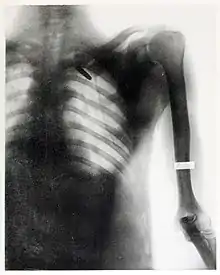

On August 20, 1899, she took one of her most famous radiographs, an image showing a Mauser 7 mm bullet lodged in the brain of John Gretzer Jr., in the region of the left occipital lobe.[12][15] Private Gretzer, of the 1st Nebraska Volunteers, wounded at Mariboa, Philippines on 27 March 1899 during the Spanish–American War. The private later returned to duty as a mail clerk.[16] Accounts of the case were reported in the 1902 edition of The International Text-Book of Surgery and in newspapers.[17] Another case of a bullet lodged in a soldier's skull, X-rayed by Fleischman was also reported in newspapers in 1899.[18]

She received praise for her work during the Spanish-American War from the Surgeon General of the Army George Miller Sternberg.[19] Several of her radiographs were also used by William C. Borden to illustrate his book on the medical use of X-rays in the Spanish-American War.[15]